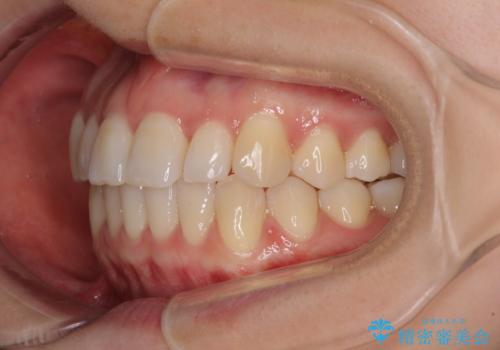

前歯のクロスバイト インビザラインによる矯正治療

- 前歯のクロスバイトを気にして来院された患者様です。

短期間での治療を希望され、ワイヤー装置とインビザラインとで悩んでいましたが、自己管理を徹底すると言うことでインビザラインによる矯正治療を行うこととしました。

しっかりとインビザラインの装着時間を守っていただいたので、1年弱で矯正治療を終えることができました。